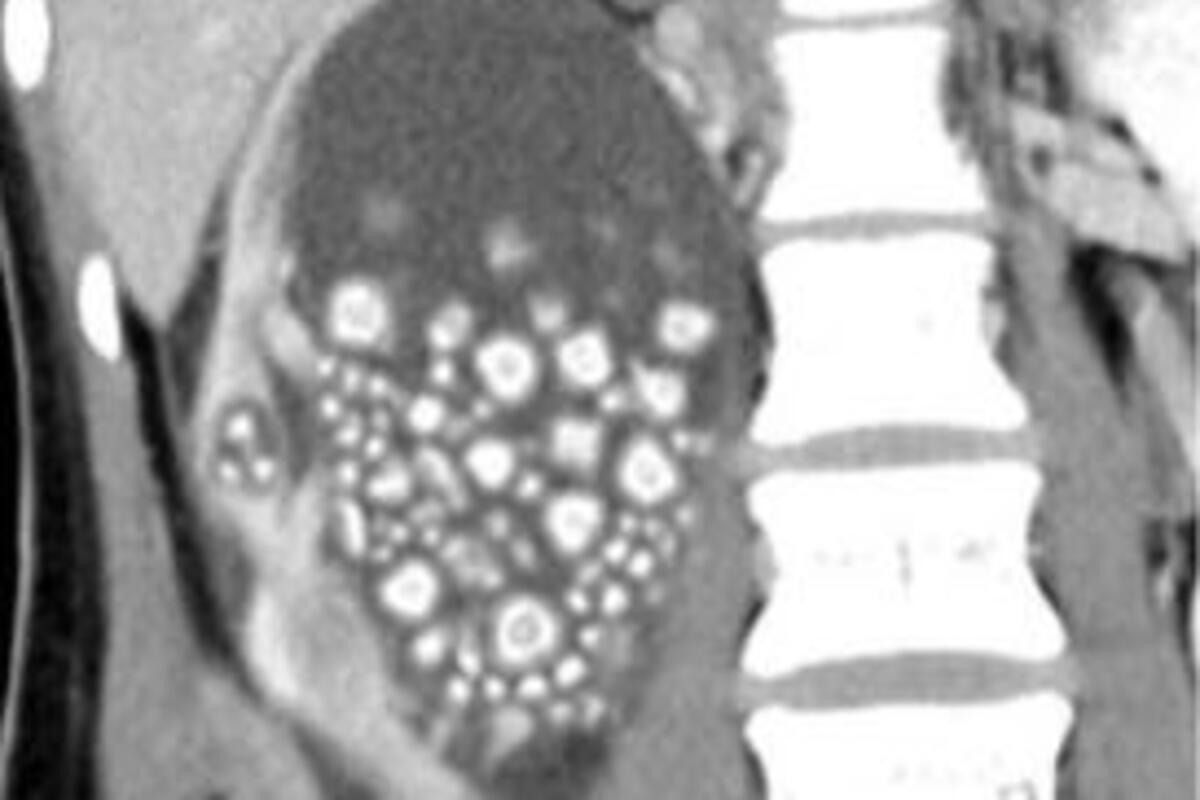

Što se tiče kamena u bubrezima, proso deluje tako što razbija kamenje, pesak i sediment u bubrezima. Takođe uspešno čisti bubrege od toksina.